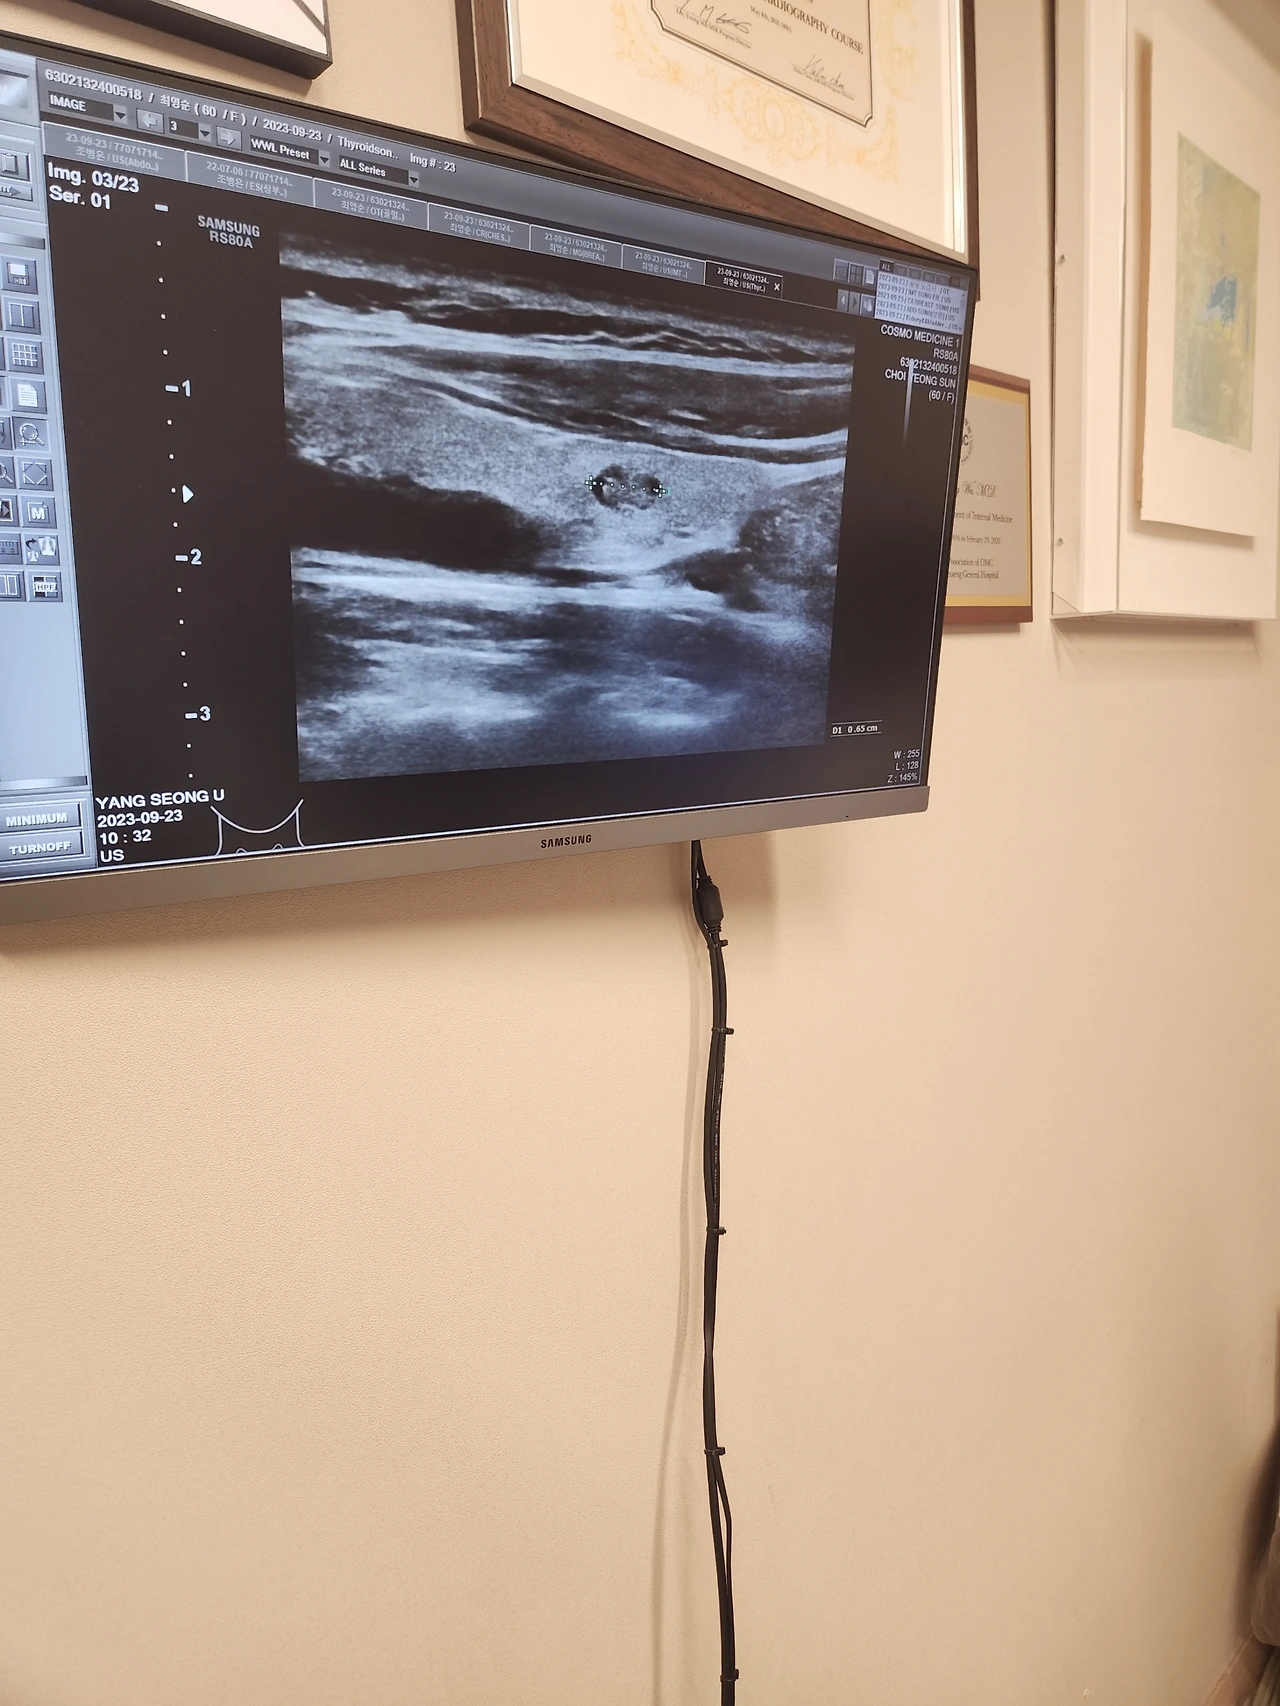

작정하고 당일에 가서 각종 초음파와 혈액 검사. 60대가 되었으니 경동맥 초음파와 골밀도 검사, 복부초음파를 추가했다. 내가 2017년도 암진단 이력이 있다보니 주의 깊게 관찰하여 꼭 추가로 넣는 검사가 있는데 종양표지자검사! 암을 예측할 수 있는 지표로 쓰인다고 볼 수 있다.

갑상선 결절 있으신거 아시죠? 그대로예요.